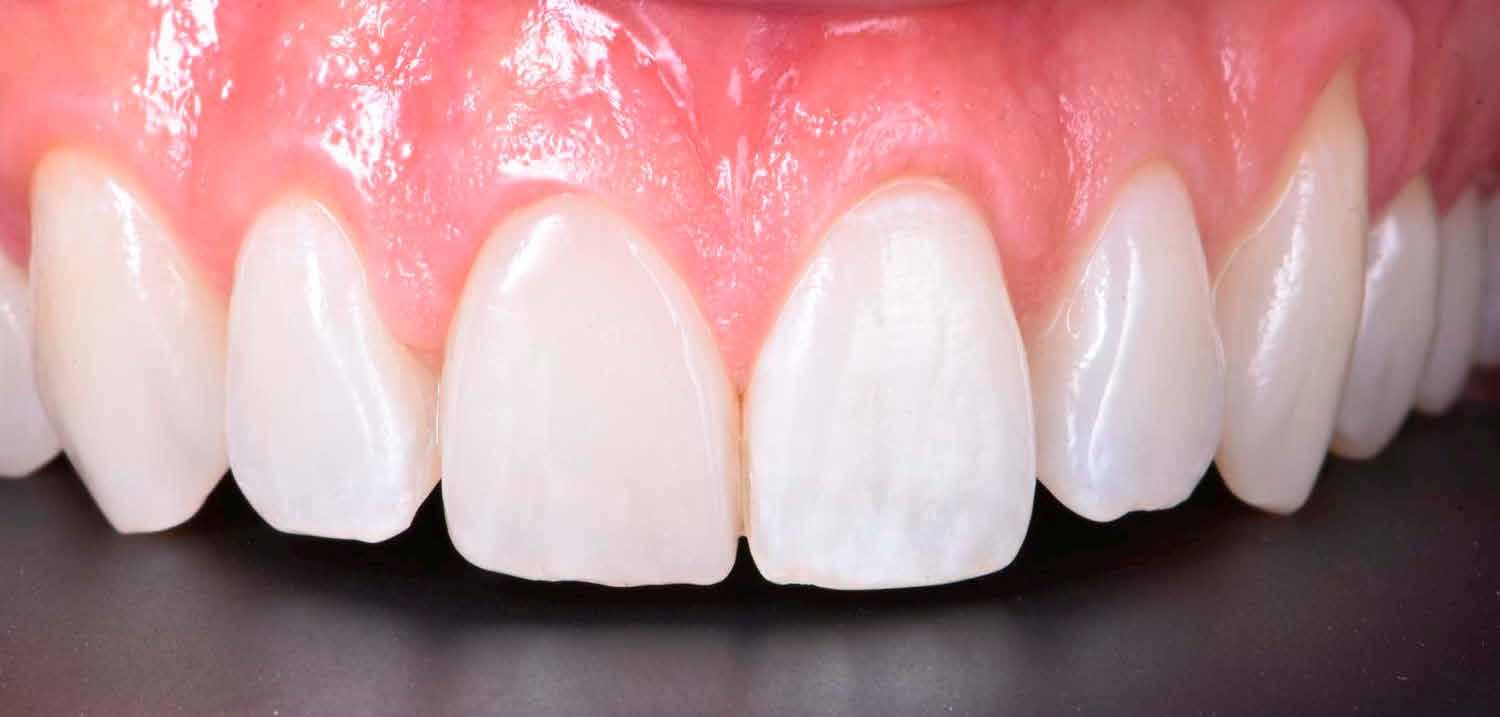

A cikkünkben bemutatásra kerülő eset ellátása során preparációt héjak készre vitele során a platinafólia technikát alkalmaztuk.

kívül vékonyak, és ezáltal a végleges rögzítésük előtt jelentős olyan minimál invazív kezelési eljárásnak számítanak, amely

elérni. A fent leírtak alapján bátran

preparációt nem igénylő héjak készítése mellett döntöttünk. A alkalmaztuk. Annak ellenére, hogy az elkészítésre kerülő héjak rendjelentős törésveszéllyel állunk szemben, összességében mégis amely segítségével kifogástalan esztétikai eredményeket lehet javasoljuk e módszer alkalmazását.

A fogászati kezelések során manapság már nem kizárólag az esztétikai megjelenés helyreállítására törekszünk. Sokszor a kedvezőtlen esztétikai megjelenés hátterében álló okok következményes módon a fogazat funkcionális működését is károsítják, így a kezelések során ezeknek a helyreállításával is foglalkoznunk kell. A különböző funkcionális és esztétikai diszkrepanciák kezelésére számtalan módszer létezik, ám ezen fogászati beavatkozások mindegyikében közös, hogy a kivitelezésük során nagyon szoros együttműködésre van szükség a kezelést végző fogorvos és a munkáját segítő fogtechnikus között. Az alábbi esetbemutatás során egy fiatal hölgypáciens fogazatának héjak alkalmazásával történő esztétikai és funkcionális rehabilitációját szeretnénk ismertetni.

1. és 2. ábra: A kiindulási és a befejezést követően látható állapot összehasonlítása extraorális felvételek segítségével.

A páciens fogazata esztétikai megjelenésének és funkcionális működésének a lehető legtöbb, saját foganyag megtartása mellett történő helyreállítása (1. és 3. ábra). A lehető legideálisabb esztétikai végeredmény elérése érdekében néhány esetben a fogak alakjának módosítá -

sára is szükség van (2. és 4. ábra).